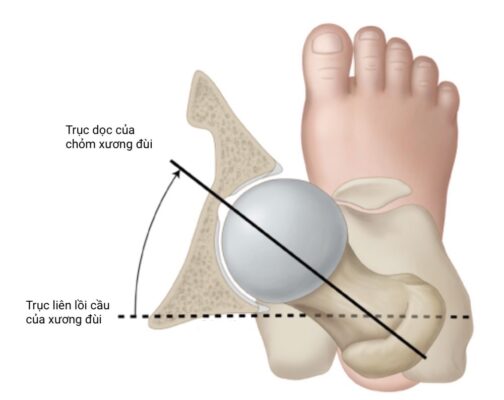

- anteversion: độ vặn ra trước của xương đùi; độ vặn hoặc gập góc ra trước của chỏm xương đùi so với mặt phẳng trán (trục liên lồi cầu).

Xoay ở háng (đùi) thường được đánh giá với bệnh nhi ở tư thế nằm sấp, háng duỗi và gối gập đến 90°. Đánh giá tầm xoay trong và xoay ngoài của khớp háng. Gia tăng xoay trong khớp háng biểu hiện vặn trước của xương đùi, ngược lại tăng xoay ngoài có thể là biểu hiện của vặn sau và đụng chạm xương đùi – ổ cối. Để xác định mức vặn ra trước của xương đùi có thể đánh giá test Craig: đo góc giữa xương chày và trục đứng dọc vuông góc với mặt giường. Góc này ở người bình thường khoảng 15 độ.